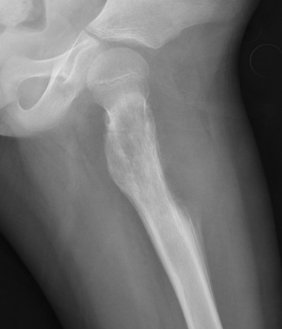

▌膨胀性破坏

膨胀性破坏是地图样破坏的特殊形式,影像学表现为骨质破坏区骨膨胀,周围可见不同程度扩张的骨壳(图 5、图 6、图 7、图 8)。膨胀性破坏是由于肿瘤从骨皮质内面破坏,骨外膜增生形成新生骨造成膨胀的。引起膨胀性破坏见于大多数良性肿瘤和肿瘤样病变如单纯性骨囊肿,动脉瘤样骨囊肿、内生软骨瘤和软骨粘液纤维瘤等,少数也可见于恶性肿瘤如转移瘤、骨髓瘤等。

图片

图 5.膨胀性破坏:动脉瘤样骨囊肿

图 6.膨胀性破坏:骨巨细胞瘤